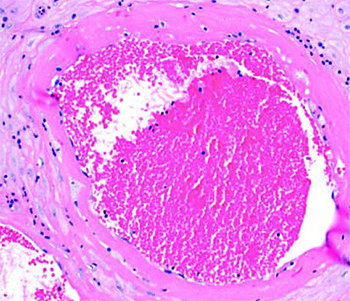

Тромбоз межворсинчатого пространства (см. рис. 4). В сосудах формируются слоистые тромбы, оттесняя на периферию ворсины, которые перестают участвовать в газообмене.

Иван Сахаров обратил внимание, что изменения настолько яркие, что видны на макроскопическом уровне. Если в норме плацентарная ткань рыхлая, насыщенного красного цвета и напоминает пропитанную кровью губку, то при тромбозе становится желтовато-серой, очень плотной и сухой. В ней имеются заполненные кровью участки — это кровоизлияния и формирующиеся тромбы.